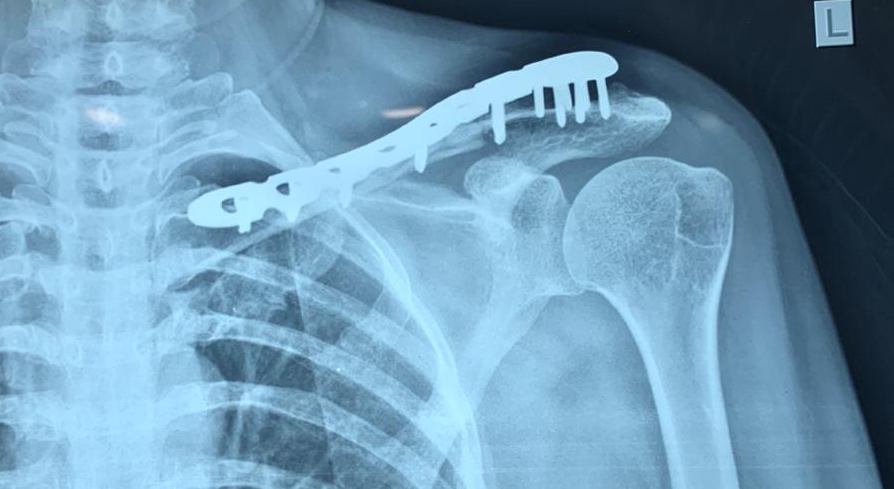

PROFILE TRAINING AND PRESENTATION Dr. Niranjanan Recieving Diploma SICOT degree in Rome, Italy Dr. Niranjanan being awarded fellowship certificate at Indian spinal injuries centre CLIINIC SOME OF Dr. NIRANJANAN's CASES